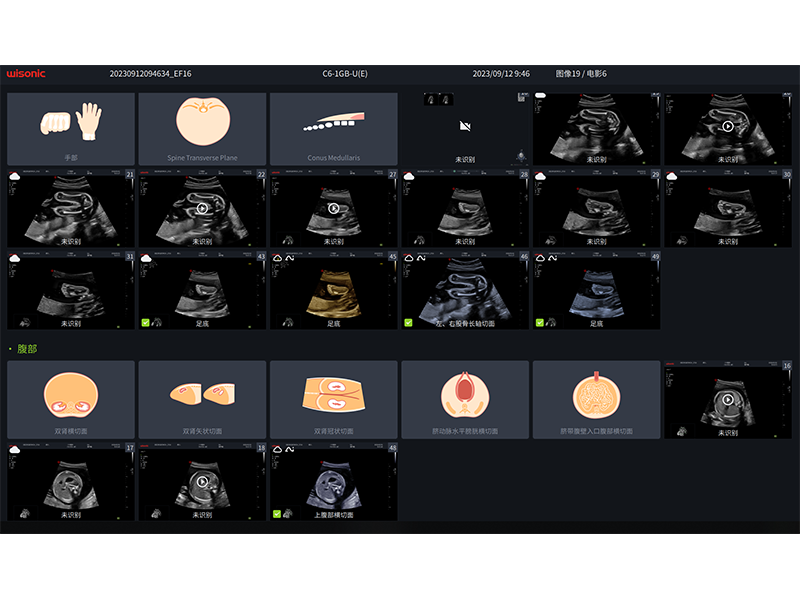

Système Intelligent d'échographie de Dépistage Obstétrical

Conceptions ergonomiques et flux de travail d'IA efficace, offrant une expérience utilisateur extraordinaire